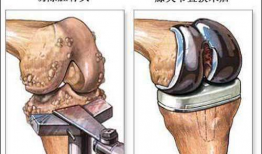

膝关节置换手术视频,从术前准备到术后康复

你有没有想过,当你的膝关节像老化的弹簧一样“嘎吱嘎吱”作响时,会有一种神奇的手术能把它换成一个全新的呢?没错,就是膝关节置换手术...

2025-12-09 37 -